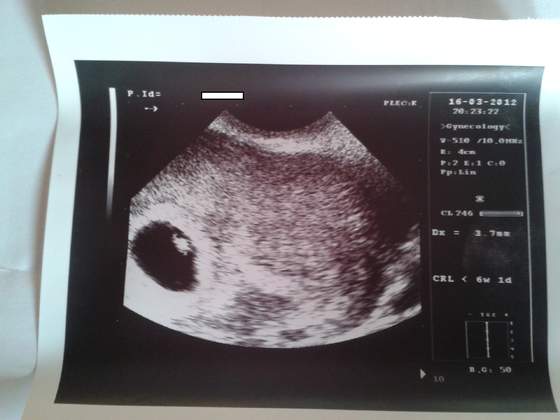

A to moje Dzidzi :) 1 wizyta 16.03.

Załączniki

• USG6TYDZ.jpg

USG6TYDZ.jpg

22,1 KB · Wyświetleń: 224